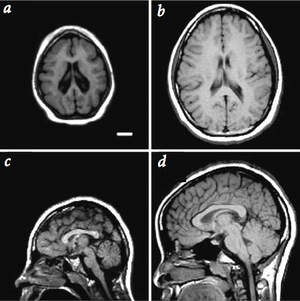

الجمجمة الصغيرة أو ميكروسيفالي Microcephaly هو وصف للدلالة على حجم رأس بشري صغير بشكل ملحوظ (بقياس المسافة حول قمة الرأس)، بحيث يكون القياس تحت المعدل الطبيعي لعُمر الشخص و جنسه، و ذلك بالإعتماد على المخطّطات القياسية.

تحدث حالة الميكروسيفالي في أغلب الأحيان، بسبب فشلِ الدماغ في النمو بنسبة طبيعية. حيث أن نمو الجمجمة محدد بتوسّع الدماغ، و الذي يجب أن يتمّ بسبب النمو الطبيعيِ للدماغ أثناء الحمل و مراحل الطفولة الأولىِ.

الظروف التي تؤثر على نمو الدماغ يمكن أَنْ تسبّب حالة الميكروسيفالي، و هي تشمل الإلتهابات، اِضطرابات وراثية، وسوء التغذية الحاد.